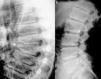

Reporte de casoPaciente varón de 17 años de edad; a los 13 años presentó dolor de cadera derecha y de rodilla izquierda. Cinco meses más tarde presentó inflamación de ambas rodillas y de interfalángicas de la mano derecha. El paciente refirió historia de dificultad al caminar desde los 3 años de edad. El examen físico mostró un adolescente con marcha anormal, escoliosis espinal y cifosis de la columna torácica. La movilidad de la columna lumbar, coxofemorales, rodillas, tobillos e interfalángicas de la mano derecha estaba severamente limitada. Las radiografías de manos y pies (fig. 1a y b), caderas y rodillas (fig. 2a y b) revelaron osteopenia difusa, ensanchamiento tubular de las epífisis y pérdida del espacio articular, sin lesiones erosivas; las radiografías de cadera y rodillas mostraron además cambios degenerativos, con cabezas femorales ensanchadas. Las vértebras torácicas y lumbares, con vértebras aplanadas e irregularidades en las mesetas vertebrales (fig. 3a y b). La proteína C reactiva y la velocidad de sedimentación globular eran normales.

La DPSR simula clínicamente una artritis idiopática juvenil en etapas tempranas1,2; sin embargo, las evidencias que establecen el diagnóstico de esta displasia ósea son la afectación articular no inflamatoria y los hallazgos radiológicos característicos, como la presencia de epífisis ensanchadas, osteoporosis generalizada y platispondilia3.